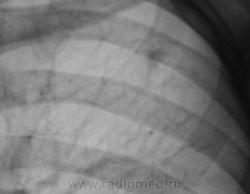

Первый срез.

Конечно, ответственность, подросток и все такое... Но с другой стороны, кроме мелкого кальцинатика прицепиться больше не к чему. Все очаговоподобные тени видны при уменьшенной яркости и в местах пересечения сосуда с кортикалом ребра. Либо имеют "хвостик", что указывает на сосуд. Такое мое мнение.